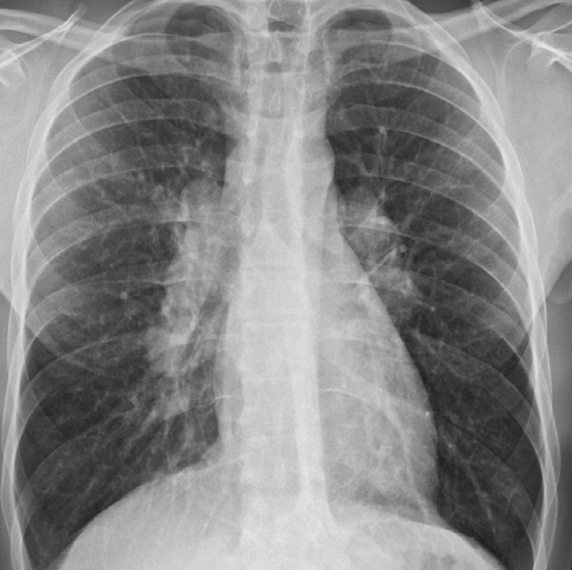

Pericardial effusion. The heart is greatly enlarged. The outline is well defined and the shape globular (Flask - bottle). The lungs are normal. The cause in this case was a viral pericarditis. // Flask shaped, pericardial effusion